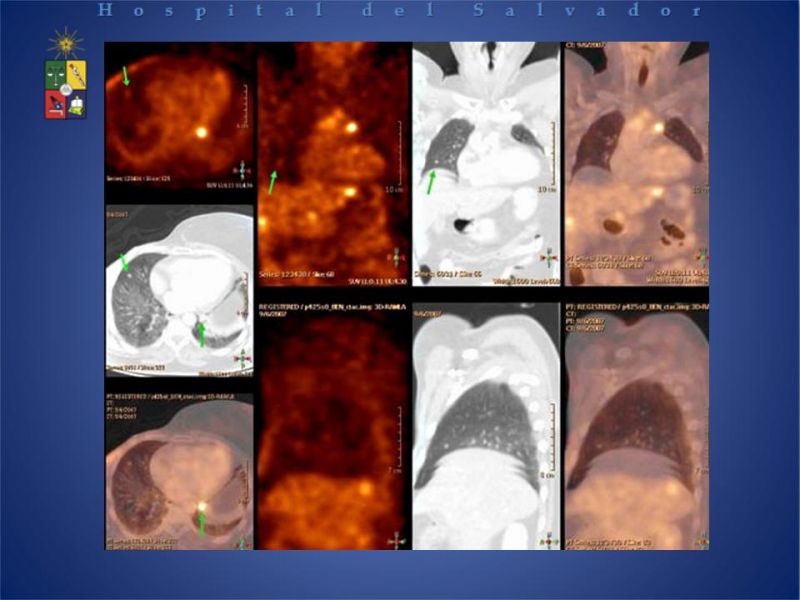

PET-CT en cáncer de Pulmón

Cirugía Cardíaca

| Autor: Dra. Jeanne Carla Palet